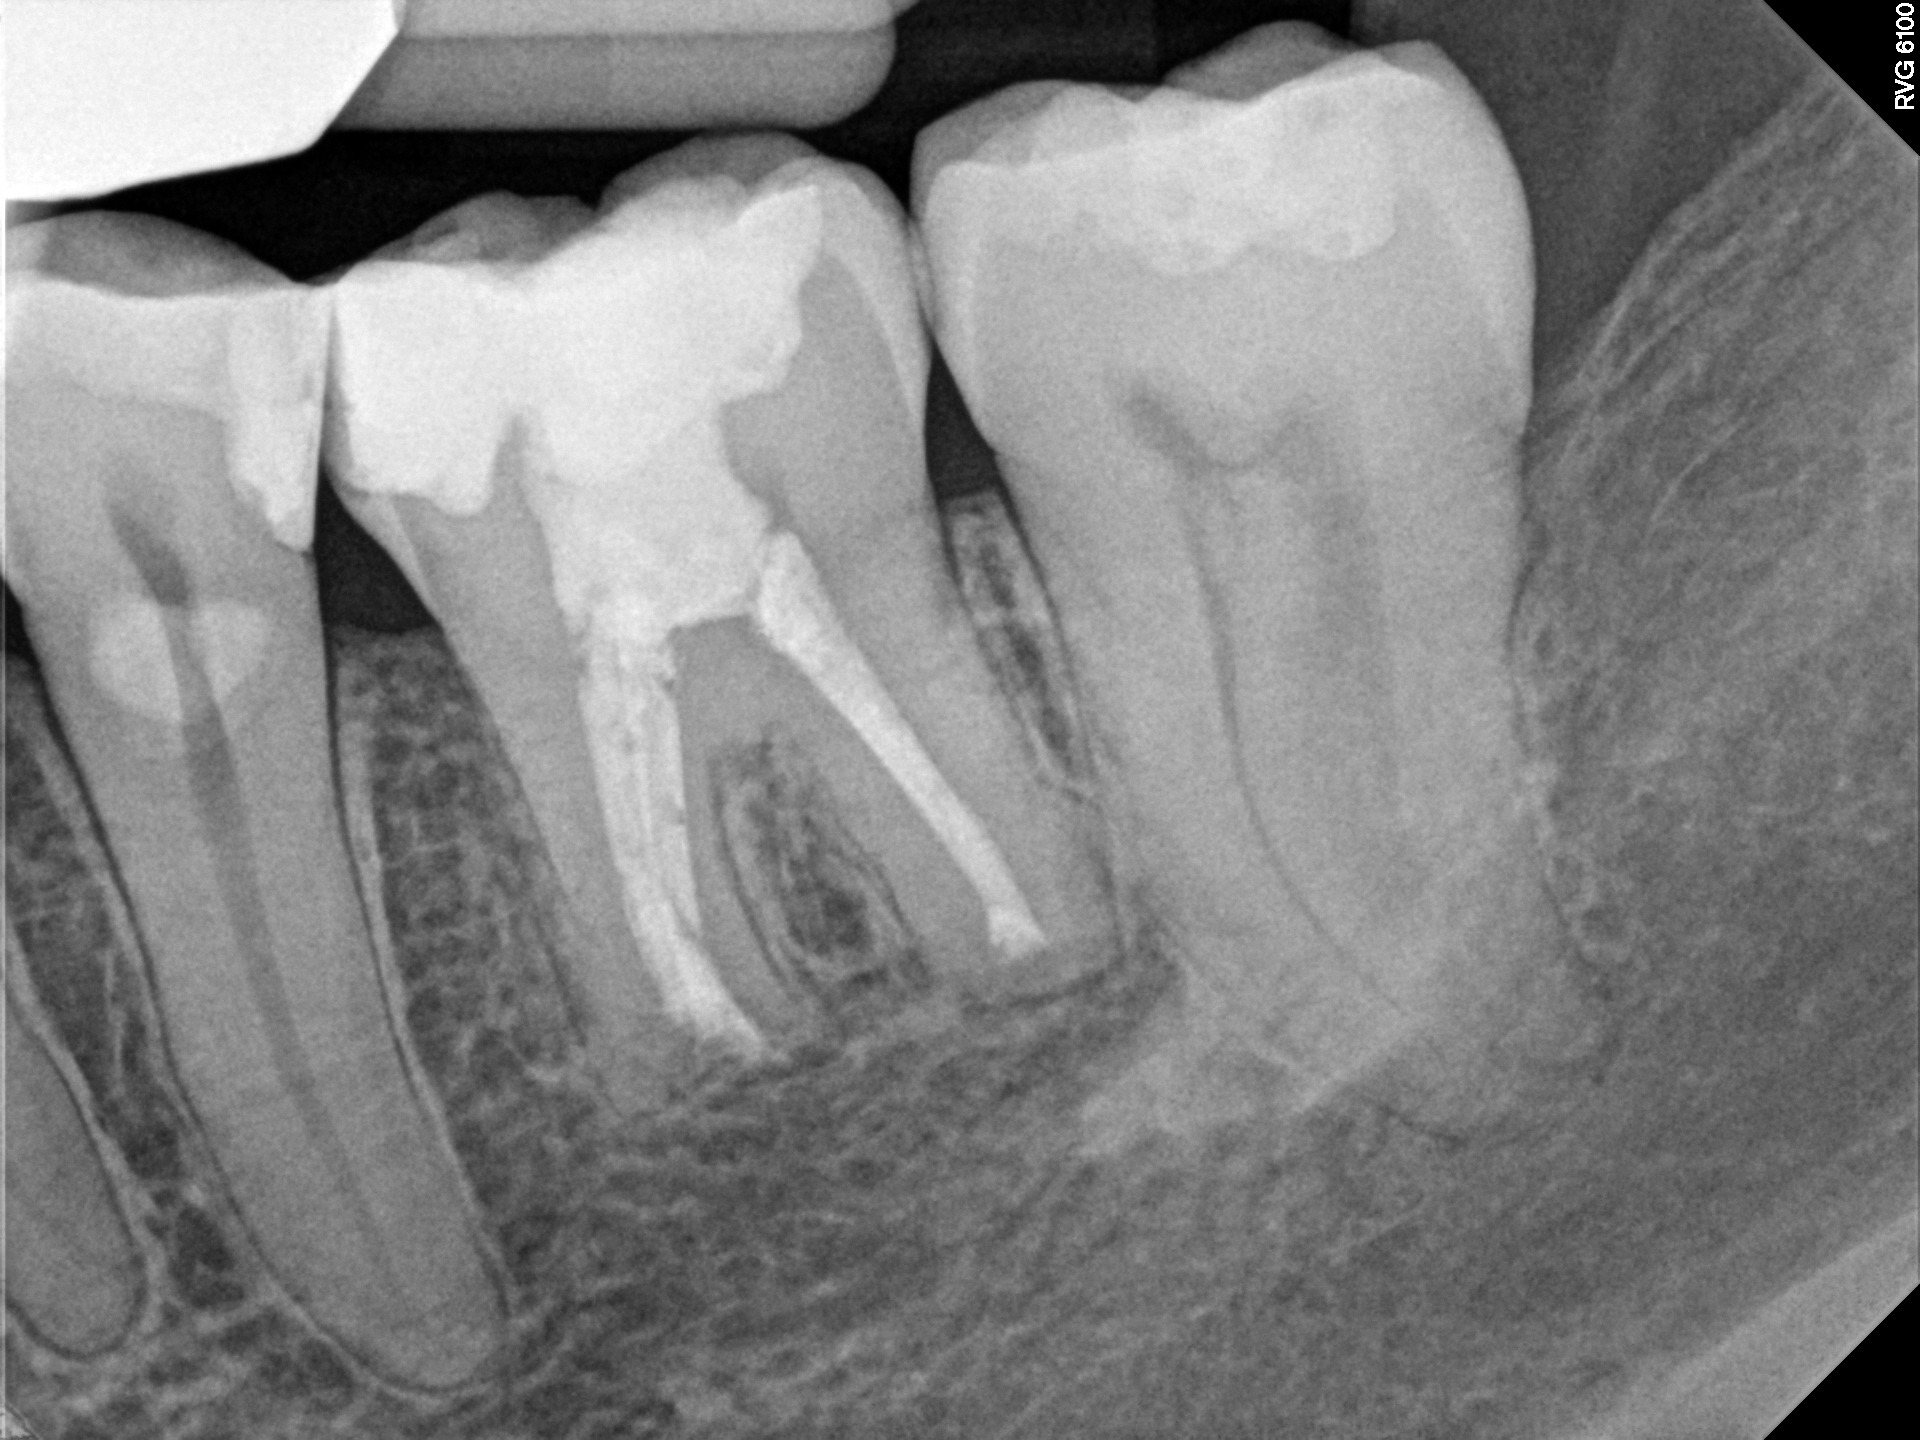

Case 2

This is a retreatment case. The picture on the left shows a lower molar that had been root canal treated many years prior, but either did not heal or at some point afterward became re-infected. The lesion is quite large, extending to the inferior alveolar nerve. While retreating the case Dr Cottle found a previously missed nerve canal (three in one root, five total in this one molar) and was able to disinfect all the canals again. The image on the right shows the completely healed bone one year later.